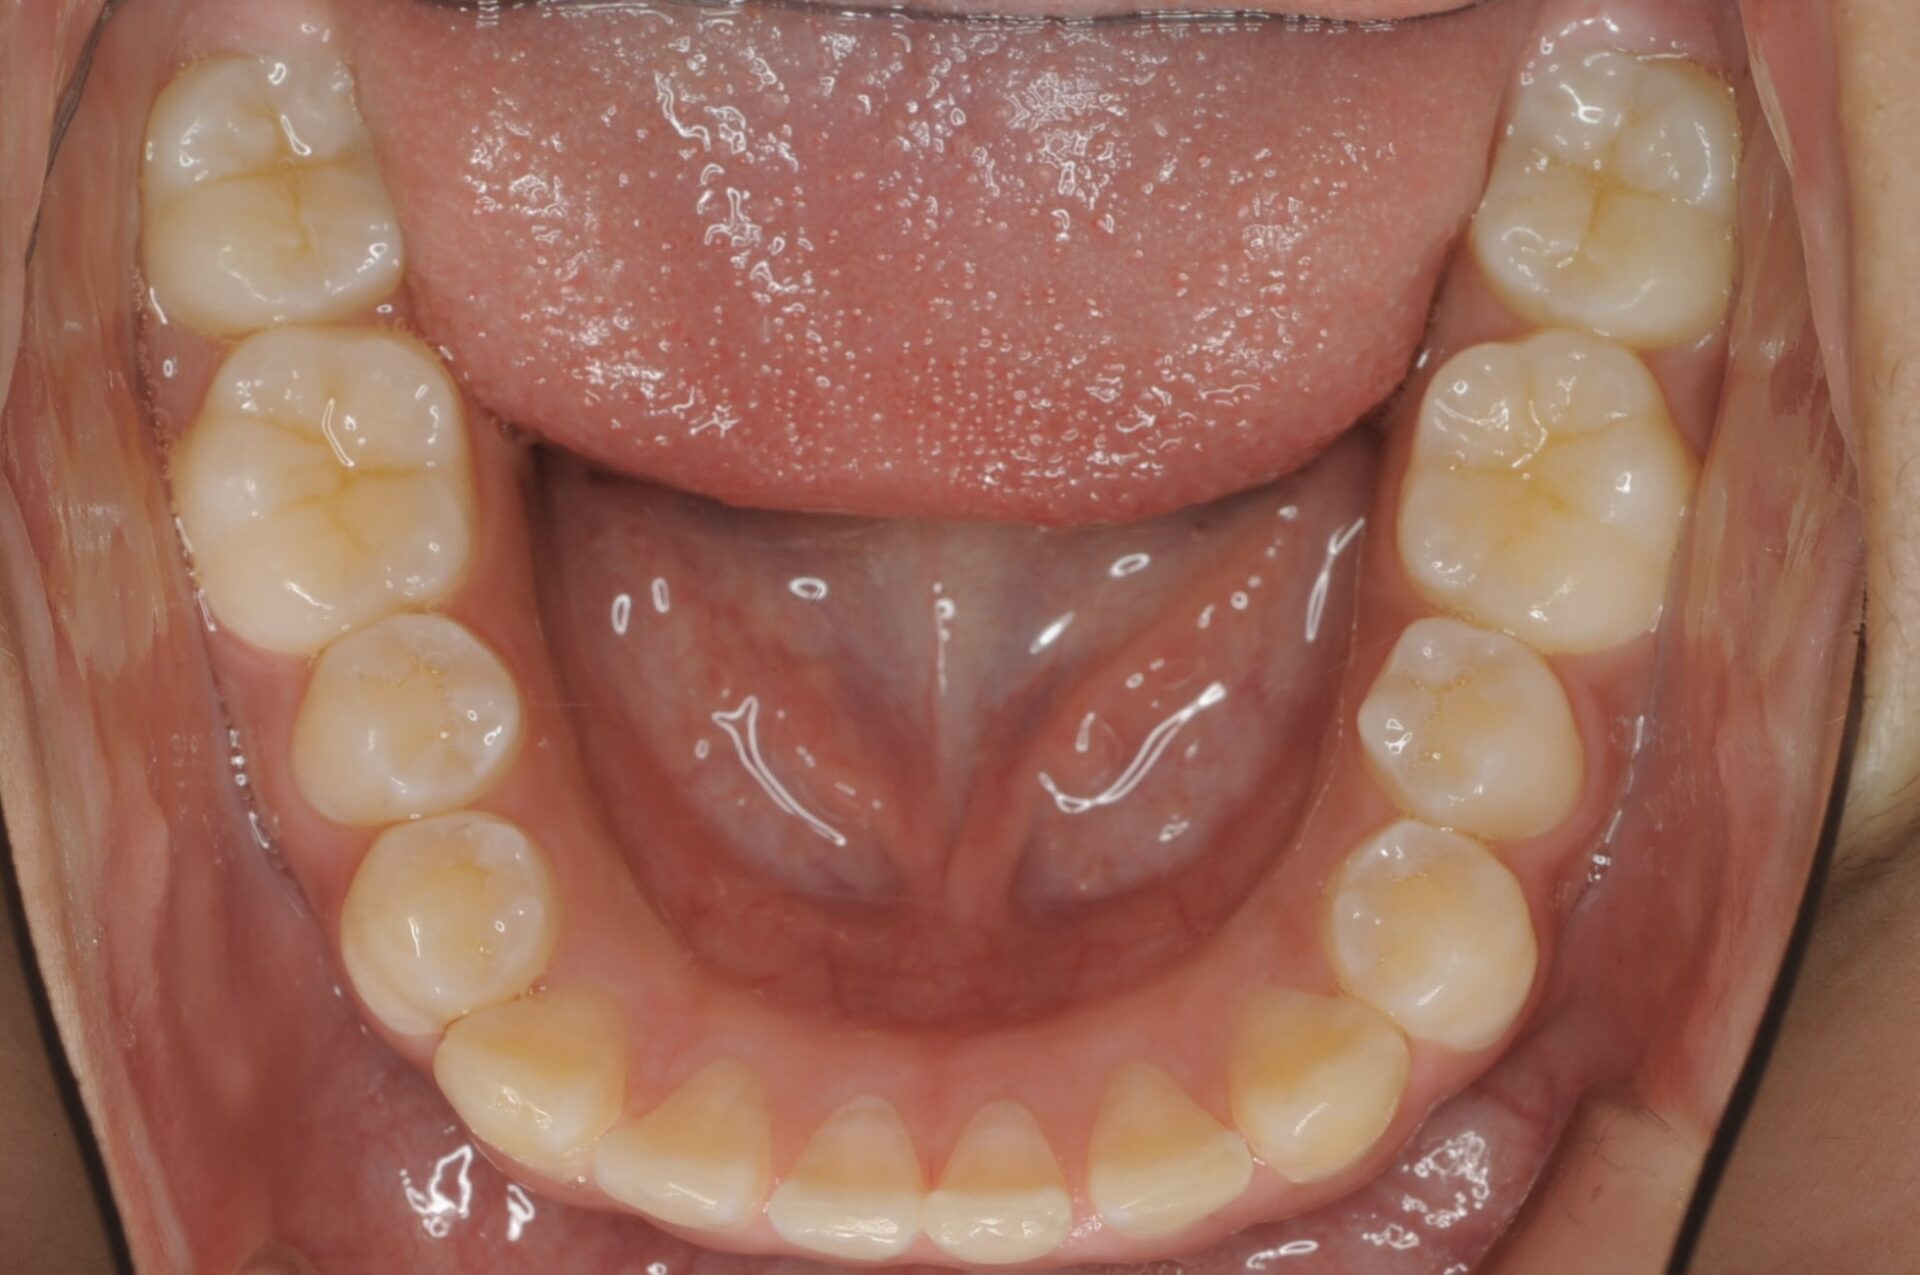

初診時(下顎)

矯正治療スタート時